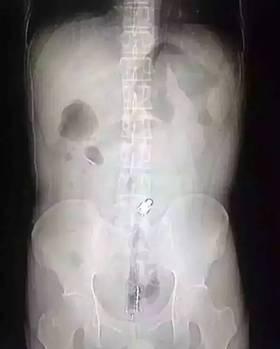

“因?yàn)槲矬w邊緣比較光滑,手術(shù)的時(shí)候,我們兩個(gè)人合作,一個(gè)人順著肚子一點(diǎn)點(diǎn)推,推到肛門口,我把異物拿了出來,大概花了十分鐘時(shí)間。”郁峰說,這名男子運(yùn)氣算好的,因?yàn)楦鶕?jù)拍片檢查,當(dāng)時(shí)那根振動(dòng)棒已經(jīng)擠到了肚臍的部位,情況其實(shí)已經(jīng)相當(dāng)危險(xiǎn)。醫(yī)生提醒 “那根振動(dòng)棒有20公分,人的直腸只有18公分,它的長度已經(jīng)超過直腸了,到達(dá)乙狀結(jié)腸,會(huì)引起腸子破裂壞死,如果破了就會(huì)有生命危險(xiǎn) 。 ”